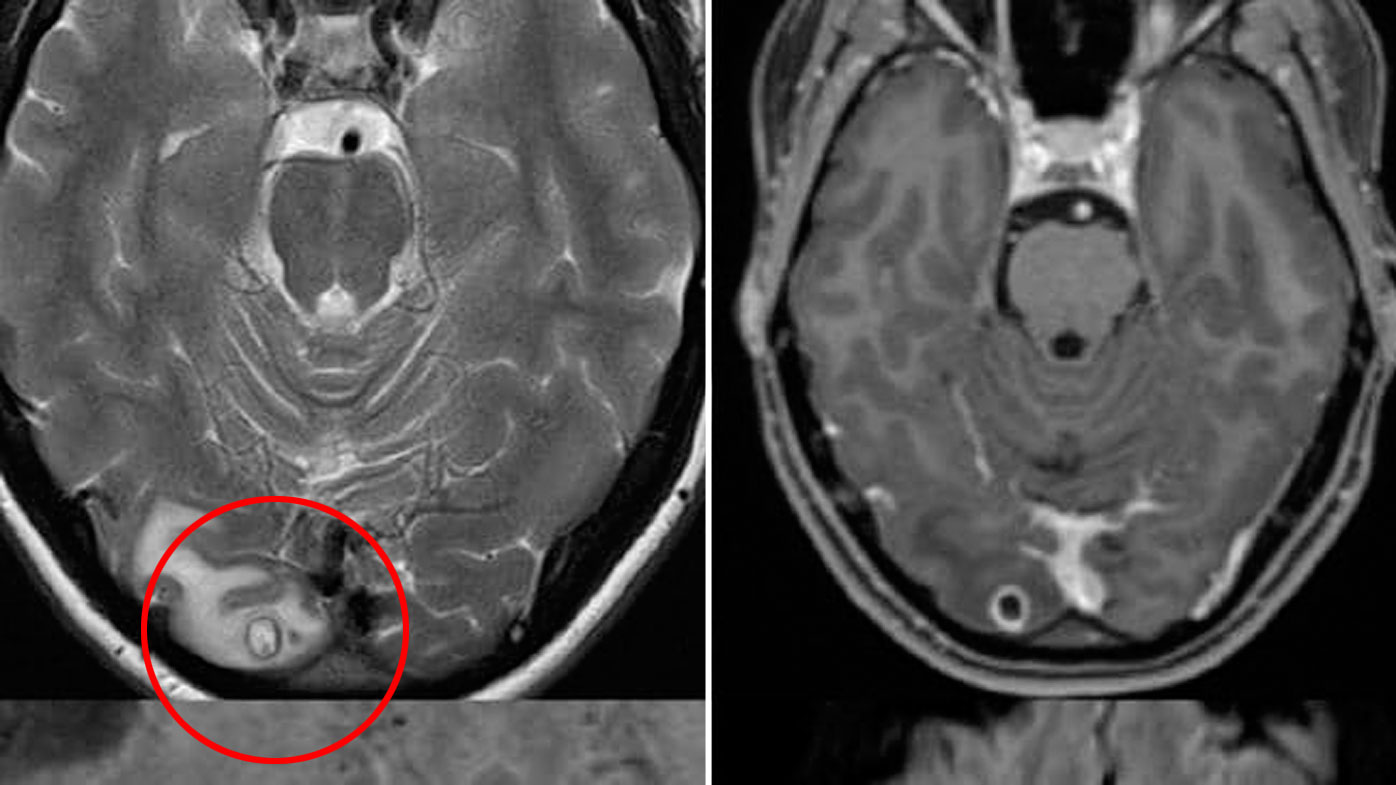

Vuante nga migrena kronike, mjekët i gjejnë vezë krimbash në trurin e tij